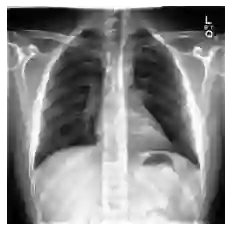

Automated diagnosis prediction from medical images is a valuable resource to support clinical decision-making. However, such systems usually need to be trained on large amounts of annotated data, which often is scarce in the medical domain. Zero-shot methods address this challenge by allowing a flexible adaption to new settings with different clinical findings without relying on labeled data. Further, to integrate automated diagnosis in the clinical workflow, methods should be transparent and explainable, increasing medical professionals' trust and facilitating correctness verification. In this work, we introduce Xplainer, a novel framework for explainable zero-shot diagnosis in the clinical setting. Xplainer adapts the classification-by-description approach of contrastive vision-language models to the multi-label medical diagnosis task. Specifically, instead of directly predicting a diagnosis, we prompt the model to classify the existence of descriptive observations, which a radiologist would look for on an X-Ray scan, and use the descriptor probabilities to estimate the likelihood of a diagnosis. Our model is explainable by design, as the final diagnosis prediction is directly based on the prediction of the underlying descriptors. We evaluate Xplainer on two chest X-ray datasets, CheXpert and ChestX-ray14, and demonstrate its effectiveness in improving the performance and explainability of zero-shot diagnosis. Our results suggest that Xplainer provides a more detailed understanding of the decision-making process and can be a valuable tool for clinical diagnosis.